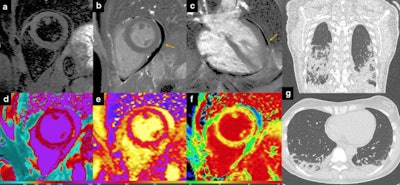

Myocarditis. 51-year-old man hospitalized for COVID‐19 pneumonia and sudden onset of tachyarrhythmias. short tau inversion recovery images revealed no edema (a), although late gadolinium enhancement (LGE) was evident on inferolateral segments of basal-mid planes with a subepicardial pattern of distribution (b, c: orange arrows) and native T1 was increased on LGE + segments (d). T2 mapping sequences revealed the presence of edema on inferolateral segments of mid-ventricular planes (e). Extracellular volume confirmed those findings with implemented values on inferolateral wall (f). Chest CT showed ground glass opacity predominantly distributed on inferior lobes with a peripheral distribution (g). All images courtesy of Dr. Federica Catapano and Prof. Marco Francone and Insights into Imaging."Rational utilization of advanced cardiac imaging services in COVID-19 should serve to avoid or at least minimize the unnecessary use of invasive, potentially contagious and time-consuming procedures like cardiac catheterization or transesophageal echocardiography and to speed-up diagnostic pathways," they said.

While bedside echocardiography remains a first-line and ease-of-use diagnostic tool, appropriate use of second-line techniques, such as cardiac CT and cardiovascular MRI, allows the reliable exclusion of coronary artery disease together with the characterization of underlying pathological substrate.